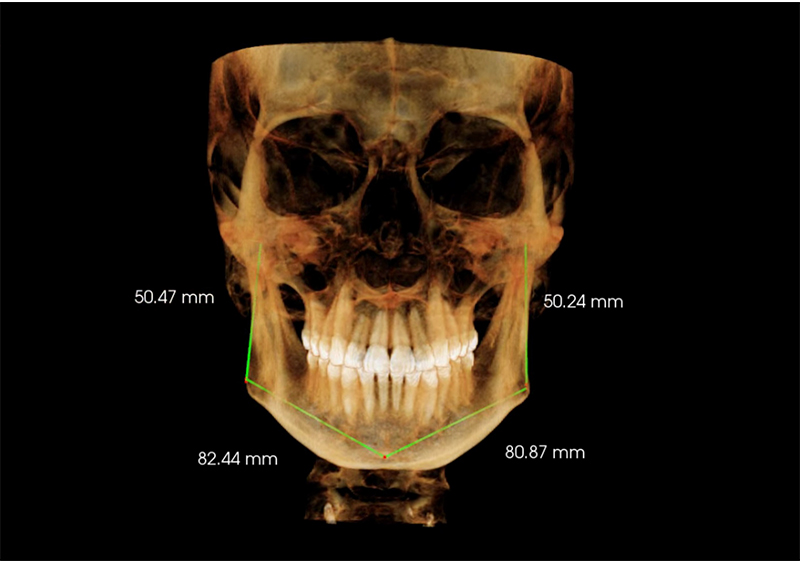

Estudio de Simetría

Nos permite analizar las distintas estructuras craneofaciales y su

relación entre si, para determinar biotipos faciales y predecir líneas de

crecimiento y desarrollo, además de posibles compensaciones